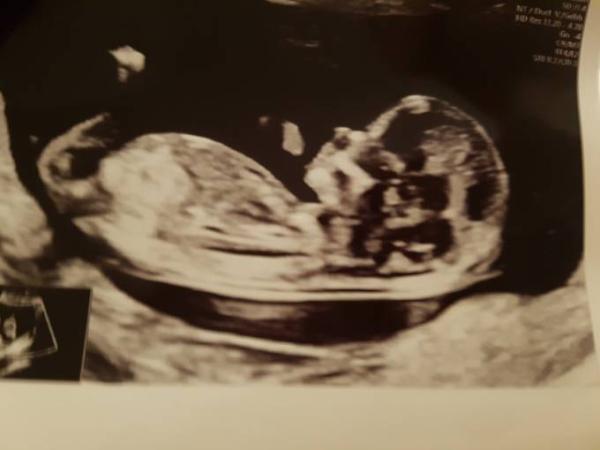

Auch ich hatte heute einen Termin beim Pränataldiagnostiker. Alles ist gut und ich bin so erleichtert Nachdem im Juli ja eine Trisomie diagnostiziert wurde sind mir hundert Steine vom Herzen gefallen und hoffe dieses mal nicht mehr vor Juli auszusteigen. Die große Schwester weiß nun auch Bescheid i Eine Tendenz zum Geschlecht hatte er wollte es aber erst in 2 Wochen mitteilen. Vielleicht habt ihr ja eine Idee ?

Bild zu Zurück von der Nackenfaltenmessung - Forum für Juli - Mamis

Dein Kind sieht auch zuckersüß aus Schön, dass alles gut ist. Da ich jetzt eine Woche vordatiert wurde, bin ich dann bei 14+3 zum Ultraschall und Harmonietest. Ich hoffe, es ist bis dahin nicht zu spät Alles Gute weiterhin Liebe Grüße Claudi